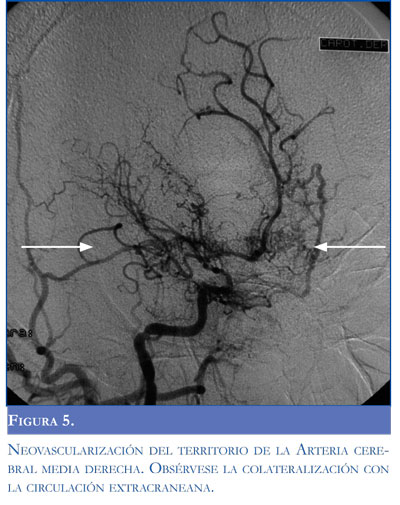

Presentación de caso. Paciente de raza negra, natural y procedente de San Pedro de los Milagros, Antioquia, con antecedente de enfermedad de células falciformes detectada a los 12 años cuando presentó déficit motor del hemicuerpo derecho, demostrándose en imágenes un ataque isquémico en territorio de la arteria cerebral media izquierda. Desde ese momento la paciente quedó con secuelas motoras. Hacia los 15 años presentó déficit en hemicuerpo izquierdo secundarios a un segundo ataque cerebro-vascular de arteria cerebral media derecha (Figura 1). Desde este momento se inició tratamiento con acido acetil salicílico, y en su evolución requirió múltiples hospitalizaciones y transfusiones.

Una arteriografía realizada durante la primera semana de evolución mostró estenosis de la carótida izquierda con adelgazamiento distal de la vascula-tura cerebral con neoformación y colateralización de circulación externa con la interna conformando un patrón típico de síndrome moyamoya (Figuras 3, 4, 5 y 6). El control imagenológico hacia los 15 días de hospitalización evidenció una disminución del 50% en el volumen del sangrado intraventricular. La paciente logró llegar a un alertamiento espontáneo sin contenido de la conciencia ni respuesta al llamado. A los 45 días de evolución logra salir de UCIN con traqueostomía percutánea y nutrición por gastrostomía.